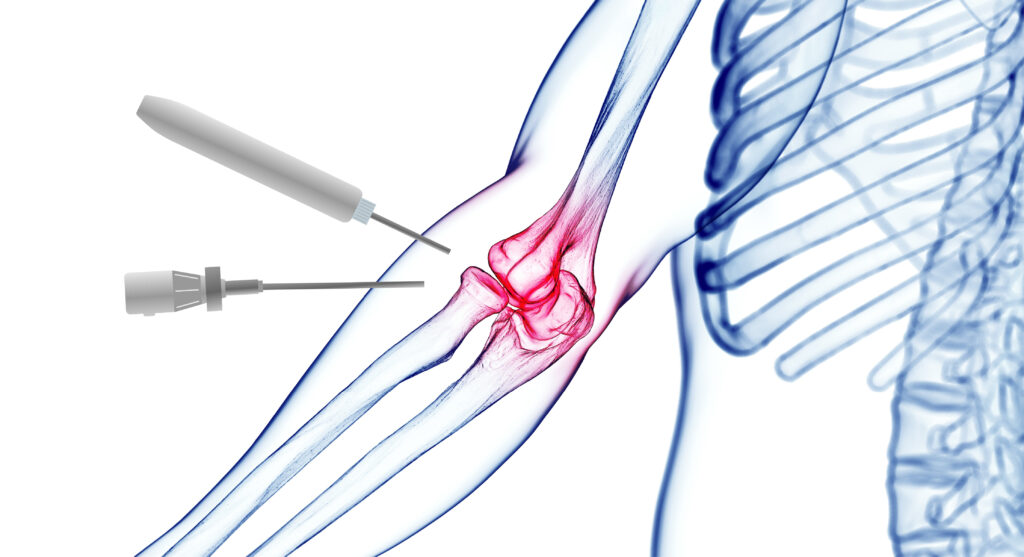

Αρθροσκόπηση Αγκώνα

Η σύγχρονη αρθροσκοπική χειρουργική των 3 αρθρώσεων του αγκώνα επιτρέπει...